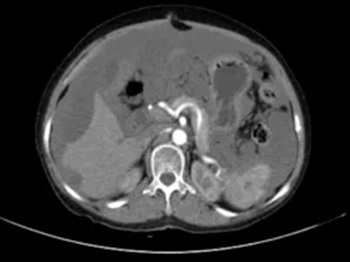

另一位80岁老年女性患者因精神萎靡、低热就诊,腹部CT检查发现其腹腔积液分布颇具特征:肝脏边缘呈“扇贝形”受压,大网膜增厚呈“饼状”。外院治疗效果不佳,遂至郑大五附院求诊。